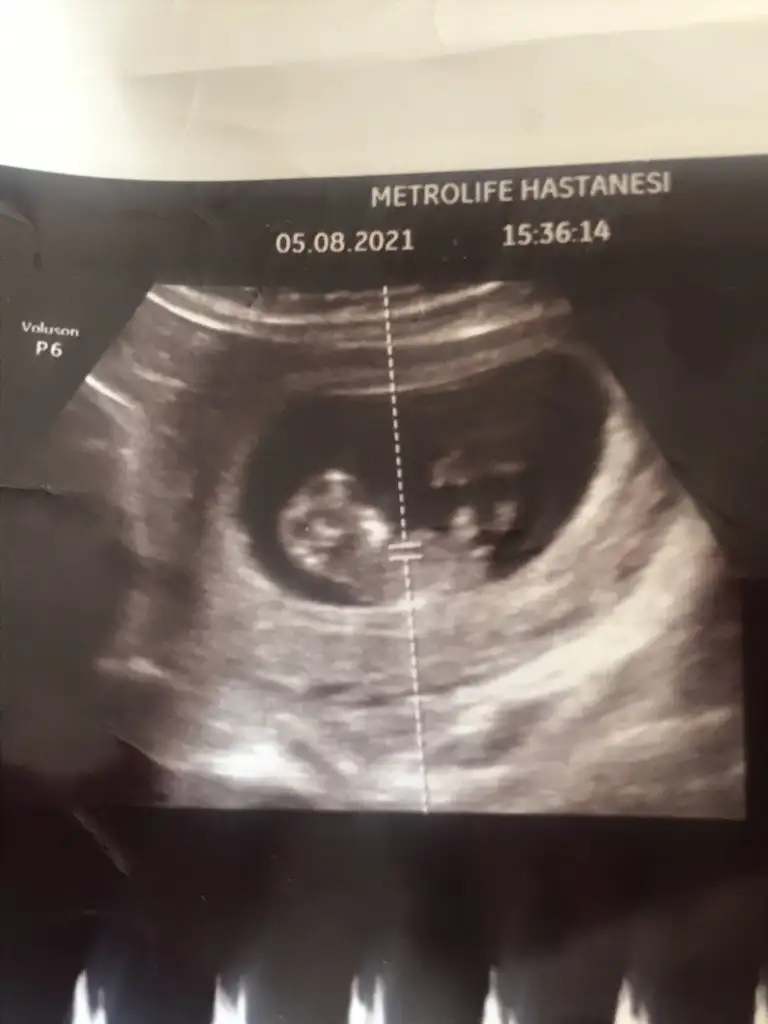

Erkek ve kız için 11 + 12+ yada 13 hafta usg görüntüsü olmalı açıklamalar asagıda yazıyorrabbim herkesin gönlüne göre nasip etsin inşallah .. ecmain

[/B]Eki Görüntüle 473828 gordugunuz gibi ust taraftaki simgedende anlasildigi gibi eger cikinti paralel ise kiz

yok 30°lik bir aciyla yukari dogru bakiyorsa %99 oglunuz olacak demektir simdi bi kac ornek resimler daha koyacagim kiziminkide dahil

Eki Görüntüle 473831 simdi burada cikintilara bakin eger bel popo cizgisine paralel ise kiz

yok 30 derecelik bir aciyla yukari bakiyorsa erkek

Net değil o nedenle yazmadım başka USG varsa paylaşın 10-11-12-13Ikra meyra bana da bir tahmininiz var mıııı yukarıda gözükmedi sanırım tekrar ekliyorum çok merak ediyorum da teşekkür ederim 12+2 günlük burda

11 12 13 haftalar olmalı şimdilik kız yönünde ama yanıltabilir dediğim gibi tekrar USG paylasin

Kız gibiEki Görüntüle 2905451 benimki de 12 hafta 3 gün çok merak.ediyorum cinsiyetini